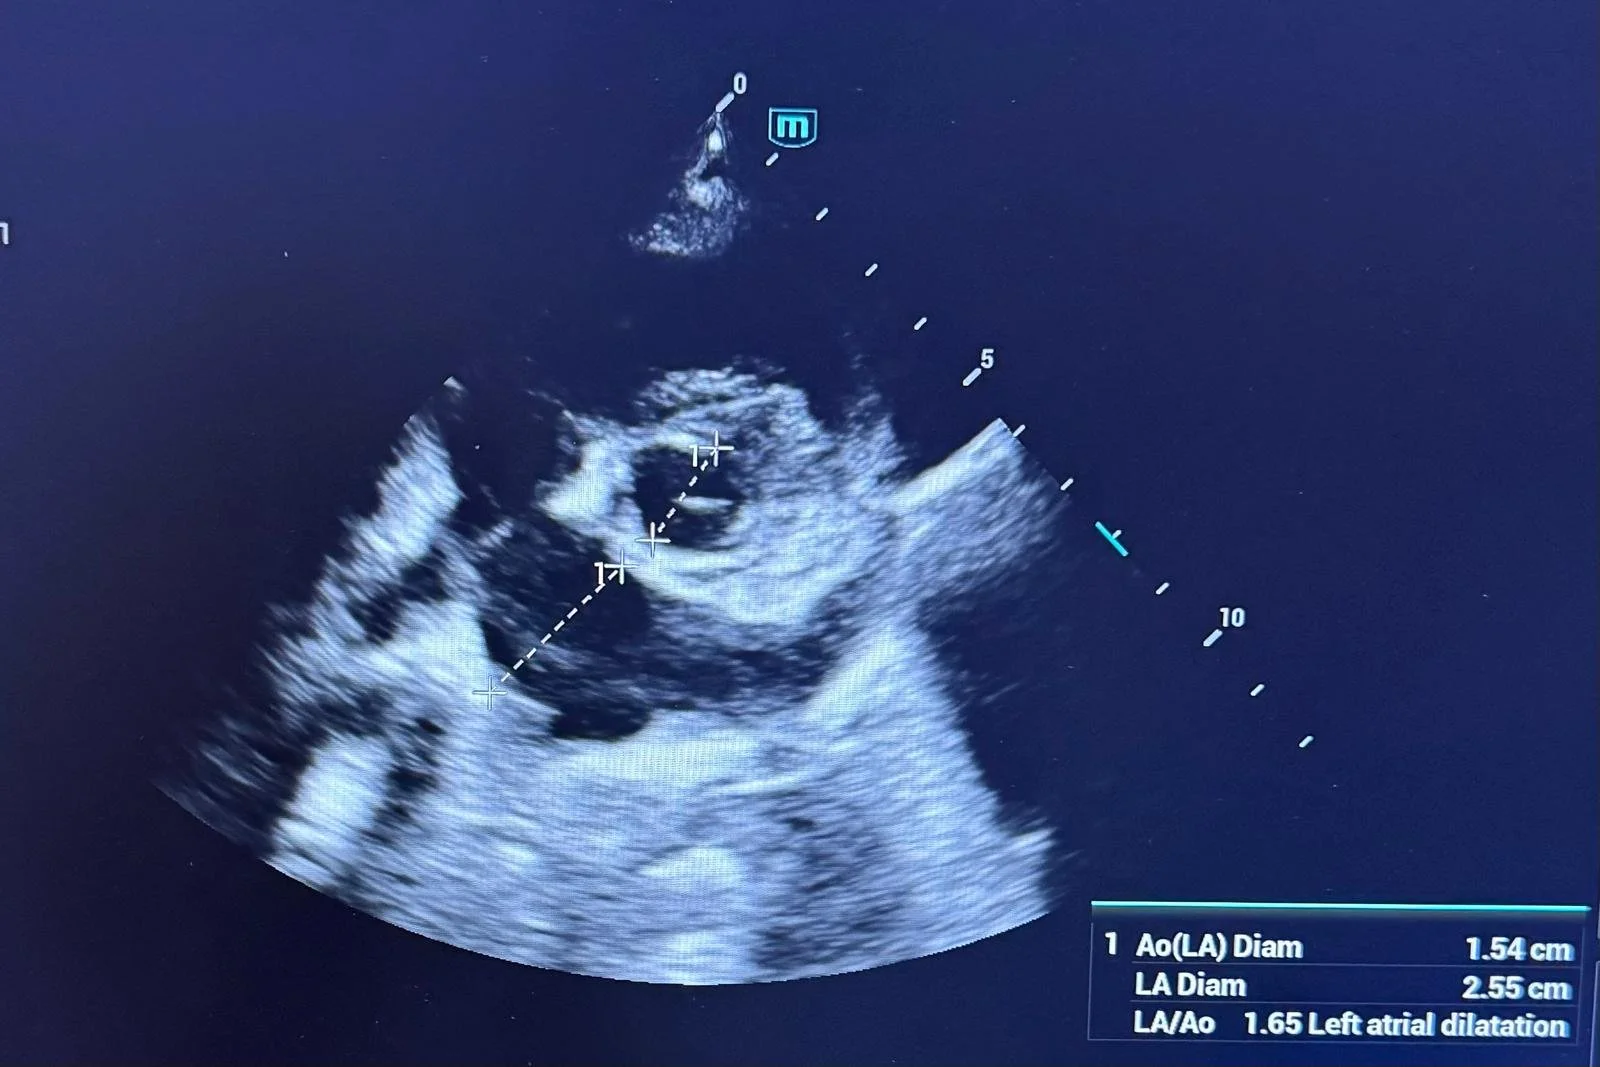

Ecografia este una dintre cele mai valoroase metode de diagnostic imagistic din medicina veterinară modernă. Deși este frecvent asociată cu investigarea unor simptome deja existente, rolul său în prevenție este la fel de important. Prin utilizarea ecografiei în controalele de rutină, multe afecțiuni pot fi depistate din timp, înainte de a provoca durere sau complicații grave.